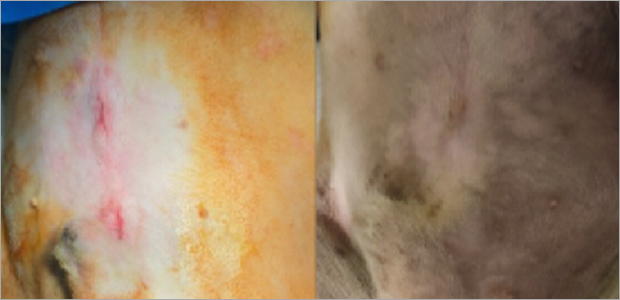

케이스1

- 수술 2주차

케이스2

치료 후기 01

강아지 중성화를 찾아보다가 복강경 중성화를 알게 되어 제일 믿을만한 예은동물병원에서

상담 수 수술했어요. 수술 전 상담에서도 친절하게 설명 해주시고 수술 과정에 대해서 상세히 알려 주셔서

믿고 맡길 수 있었어요! 수술 후에 며칠동안은 힘들어 했지만 금방 회복해서 다시 뛰어다니는 모습에

너무 감사했어요. 실밥 제거 후에도 상처 없이 잘 아물어서 만족합니다.

복강경 수술을 고민하시는 보호자님들에게 예은 적극 추천합니다.